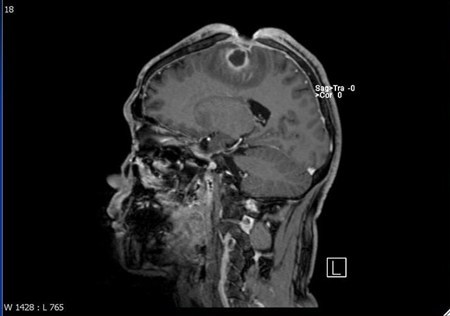

結果陳先生竟然在自己的腦袋挖出5×3×2公分的傷口,這一年期間,他生活、上班一切都沒有異狀,只是習慣用戴帽子的方式將傷口遮住,所以家人同事都沒有發現異狀,結果因為傷口感染,出現類似中風的狀況,家人在協助送醫之後,才知道陳先生竟然將自己的頭骨,腦膜都給挖破了。

傷口因為感染嚴重,醫生除了使用抗生素治療了3個月,還進行清瘡和顱骨重建手術,潘建志表示,這類患者在治療時必須先建立雙方信任關係,才能說服病人進一步治療。病人也因為腦部感染的後遺症,導致右側肢體無力,而復健長達半年的時間。